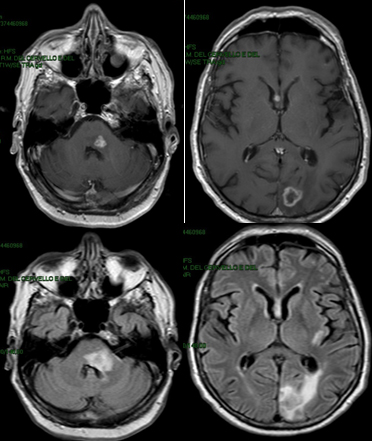

Un virus de la prolifération

Cas Clinique

Dr Anna Luisa Di Stefano Paris

Homme, 62 ans.

Consultation aux urgences pour :

- paresthésie hémiface gauche,

- parésie faciale gauche périphérique,

- hypoesthésie de l'hémicorps droit,

- vertige et déséquilibre.

Temps d’installation : 1 semaine

ATCD :

• Glaucome en OD

• Lupus érythémateux systémique avec néphrite lupique (depuis 6 ans) traité par prednisone 50 mg/jour et mycophénolate 2gr/jour depuis 2 ans

• HTA

• BPCO

Examen neurologique